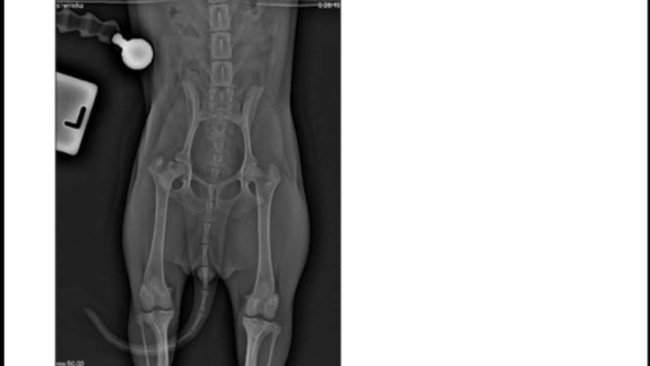

Dzień dobry nasz ukochany piesek NELA ma dopiero 7 miesięcy na początku było wszystko okej jednak jak miała 4-5 miesięcy zaczęła utykać na łapkę poszliśmy więc do lekarza okazało się że umiera jej mięsień w łapce i trzeba to jak najszybciej operować niestety nie mamy takich funduszy bardzo prosimy o wsparcie.